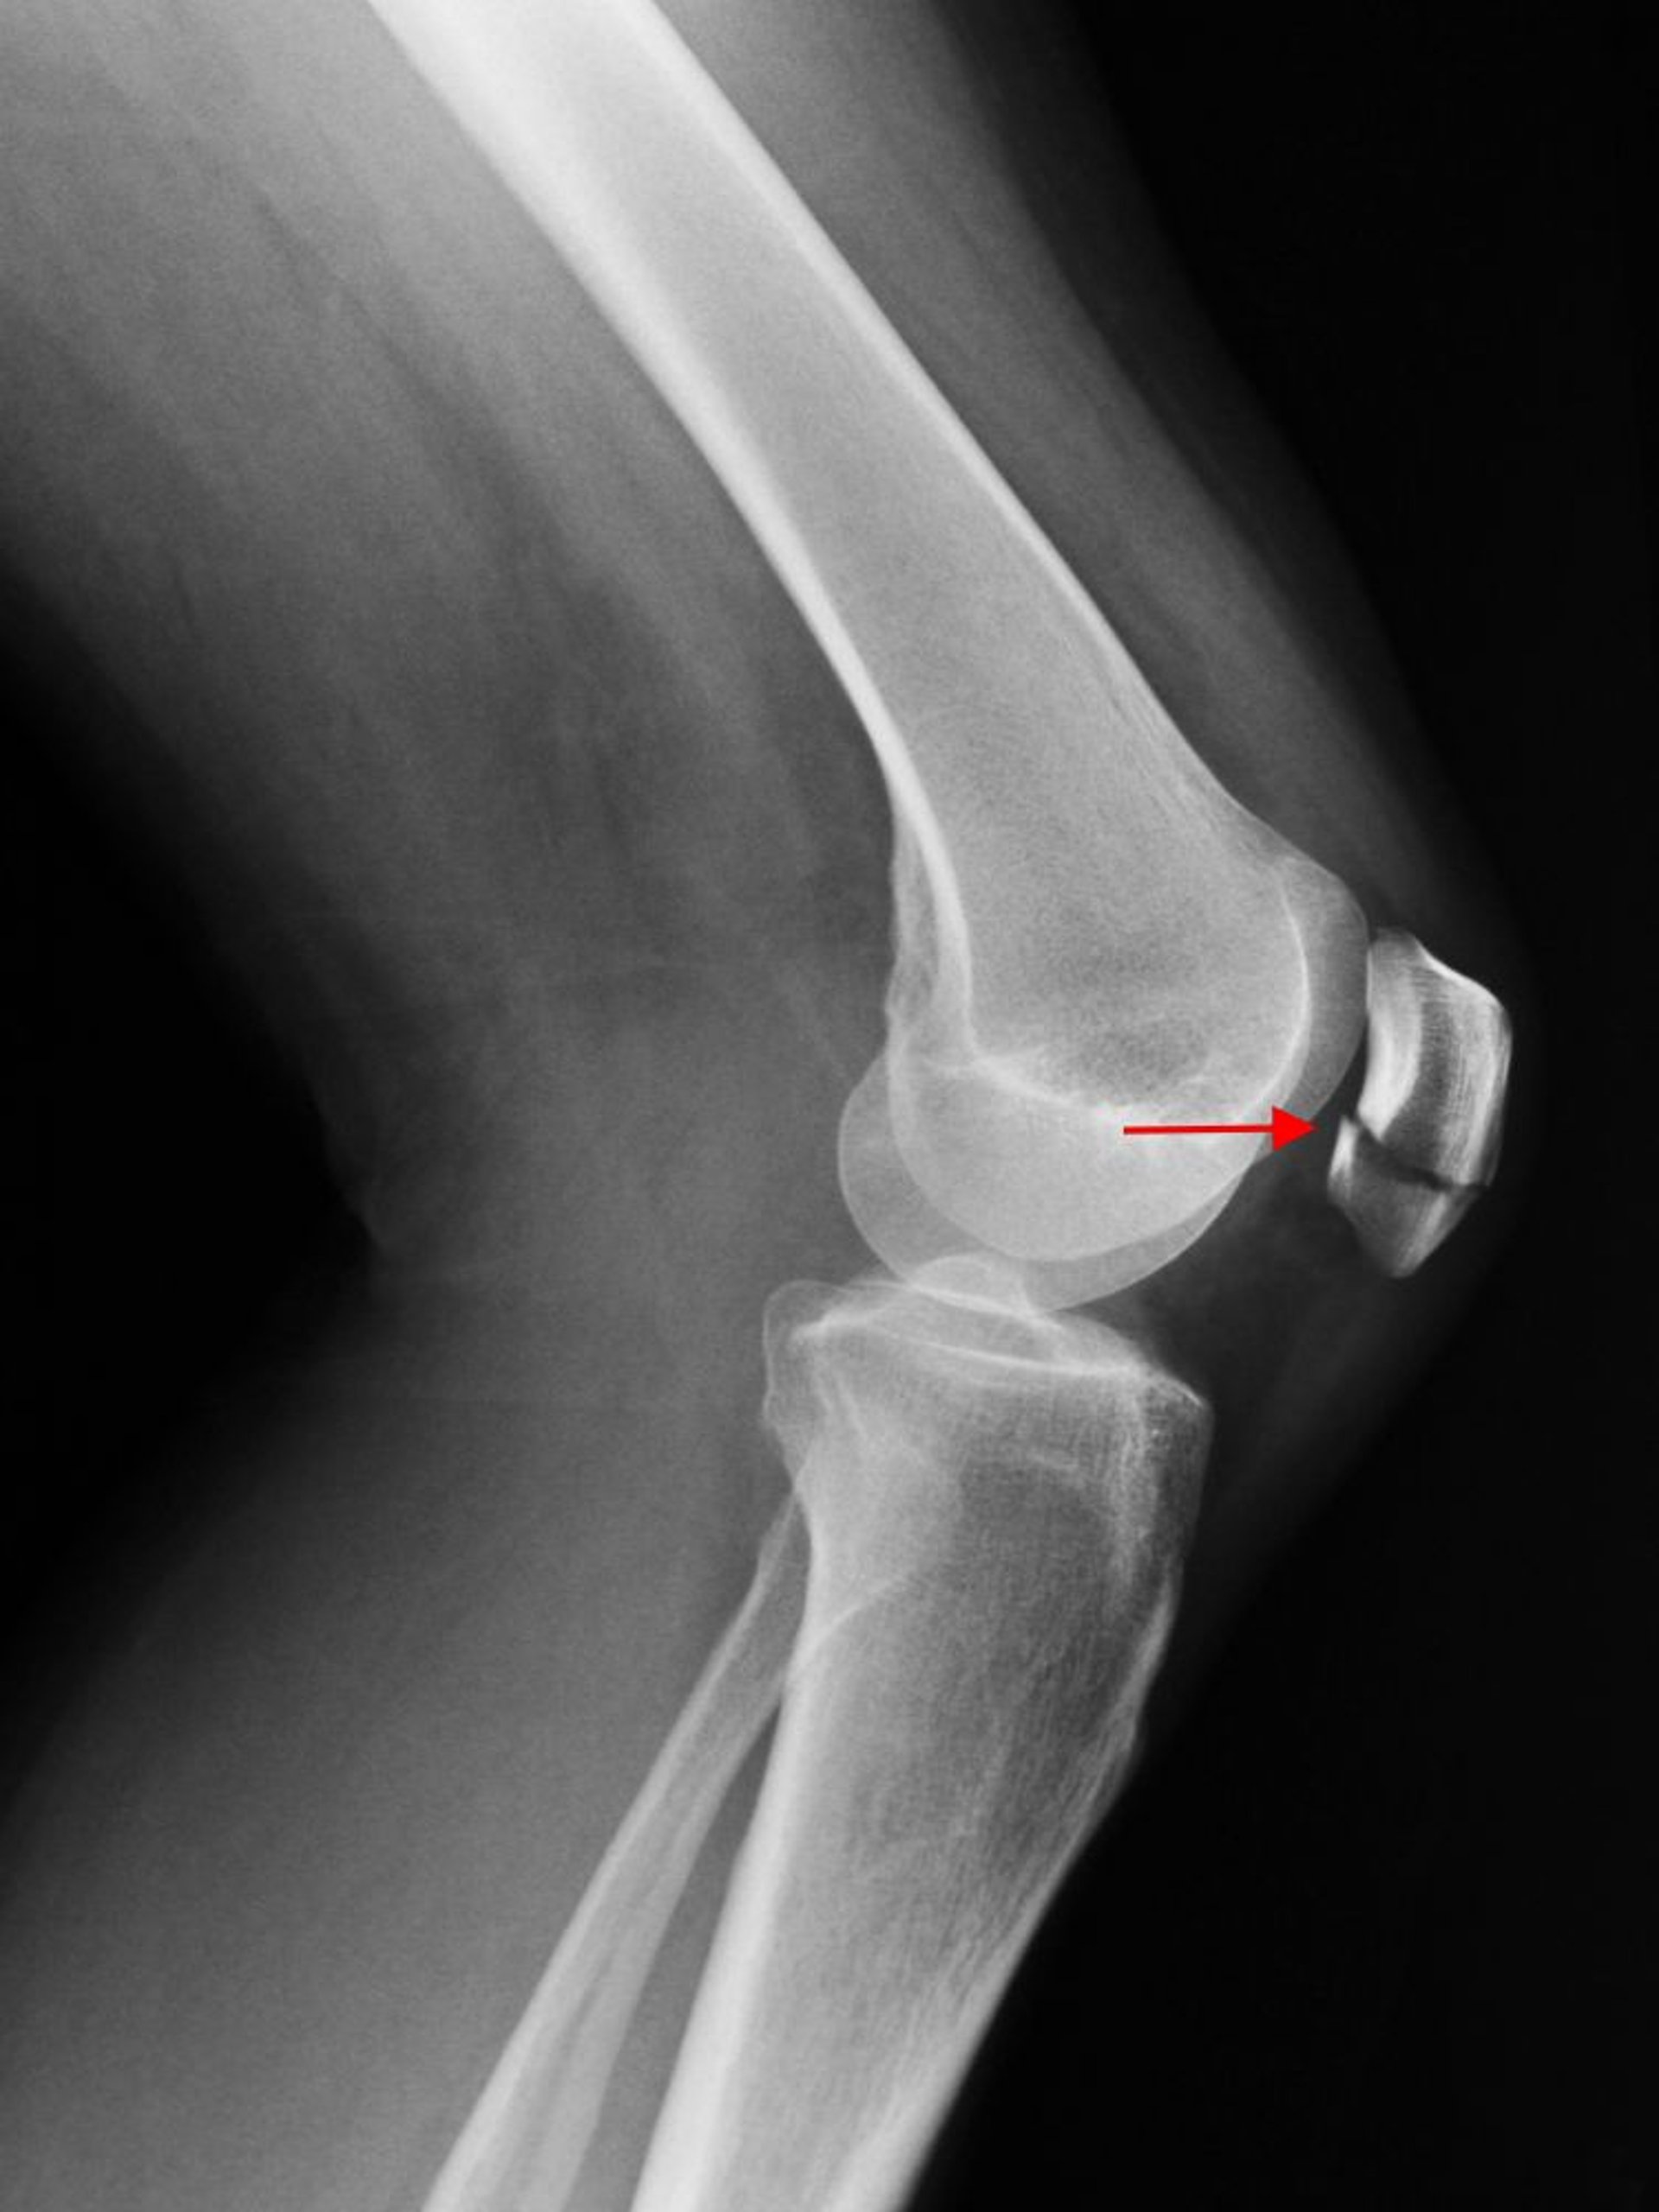

膝蓋骨骨折

膝関節のX線側面像で膝蓋骨の横骨折(矢印)が認められる。

SCOTT CAMAZINE/SCIENCE PHOTO LIBRARY